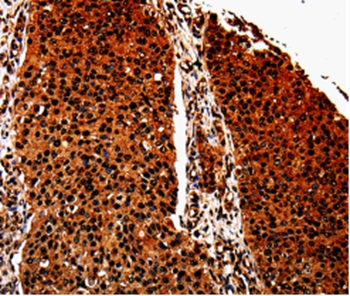

Immunohistochemical analysis of paraffin-embedded Human lung cancer tissue using #35568 at dilution 1/40.